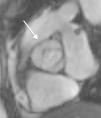

In almost all the cases, BAV results from fusion of the right and left coronary leaflets, while the fused right coronary and non-coronary leaflets variant is much less common4,14 (Figure 2).